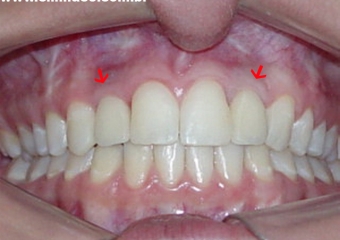

Imagem das próteses instaladas sobre os implantes

Imagem final do caso terminado em janeiro de 2008